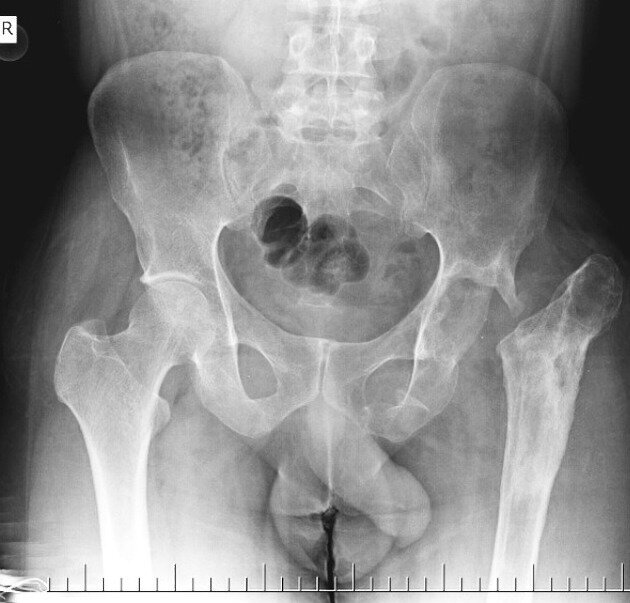

ЗНАК ТРОКМОРТОНА. Фото с сайта https://radiopaedia.org/articles/throckmorton-sign-pelvis?lang=us

Дело вот в чём. Когда скорая помощь привозит пациента с травмами таза и ему делают рентген, доктору потом нередко приходится всматриваться в снимок в поиске места поломки. И как раз тут действует правило: различимый на снимке в виде тени пенис (он же "Джон Томас") указывает на местоположение односторонней патологии (например - перелома). В данном случае врачи говорят о "положительном ЗНАКЕ ТРОКМОРТОНА". Если же тень направлена в противоположном направлении - это "отрицательный ЗНАК ТРОКМОРТОНА".

Объясняется это тем, что, предположительно, человек с переломом бедренной кости может пытаться лечь на поврежденную сторону чтобы обездвижить перелом и снизить болевые ощущения. И его детородный орган в таком случае наклоняется вниз, в сторону повреждения.